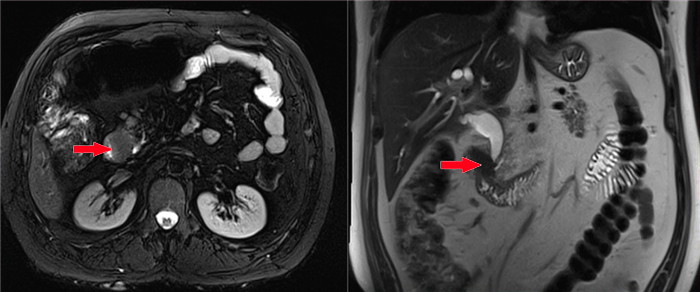

MRCP(磁共振胰膽管造影)檢查

經(jīng)過與患者詳細(xì)溝通,醫(yī)生為患者進(jìn)行了CT、MRCP、胃鏡等相關(guān)檢查,以明確患病原因、病灶位置等情況。經(jīng)相關(guān)檢查及醫(yī)生診斷,患者被診斷為十二指腸腫瘤,而且腫瘤已經(jīng)侵犯到胰頭。